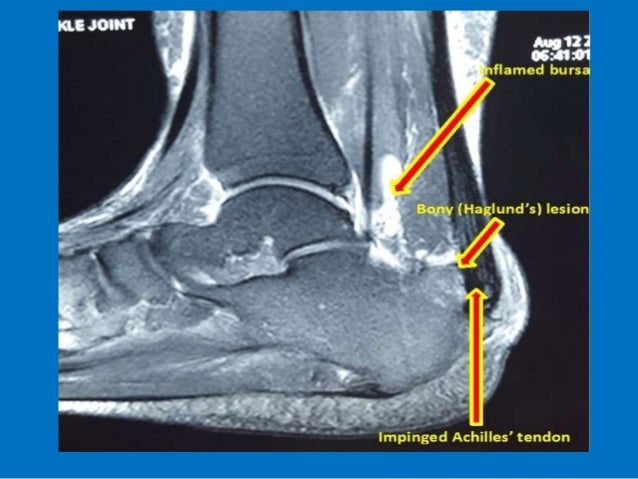

This article aims to frame a general concept of an mri protocol for the assessment of the ankle. The ankle joint is also supported by nearby tendons. Mri anatomy of the ankle tendons and ligaments.

The mri ankle protocol encompasses a set of mri sequences for the routine assessment of the ankle joint. This is the strongest largest bone of the lower leg. The ankle joint is also supported by nearby tendons. The ankle supports the weight of anatomy ▶ lower limb ▶ joints and ligaments ▶ ankle joint (talocrural joint).